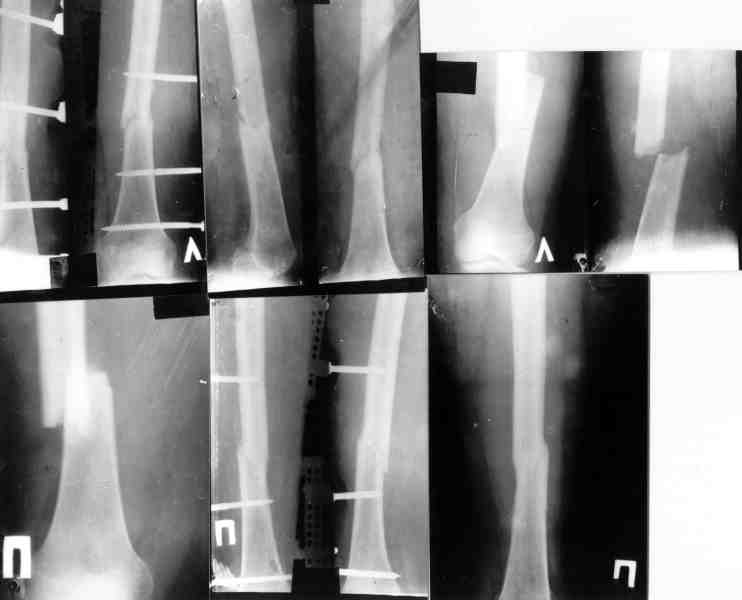

Ув. Михаил Викторович. Вы писали, что около 10 лет применяете стержневые аппараты, но они не обладают репозиционными возможностями. У нас был

разработан такой аппарат (авторы: Тауфик Амро, Сушко Геннадий Александрович (ученик Илизарова)). Манипулируя узлами данного аппарата возможно закрыто устранить любые смещения, за исключением ротационных.

Высылаю

видеофайл (несколько неудачный, но смысл понятный) - Аппата Амро широко применяется в Запорожье, Мелитополе, Приморске.

Изготовить его особого труда не составляет. У нас в Приморске своими силами мы изготовили 10 таких. Если Вас это заинтересует - вышлю чертежи, и др. информацию.

Привет Сергей. Открыл почту и сразу Ваше послание. Видеофайл отличного качества. Мы применяем стержневые аппараты описаные в руководстве по внутреннему остеосинтезу Мюллера. Они российского производства и в них отсутствует ряд компонентов репозиционного свойства. В прошлом веке принимал участие в базовом цикле АО в Н.Тагиле, где нас учили в том числе применению стежневых аппаратов. Те аппараты были со всеми примочками и можно делать репозицию во всех плоскостях. Просто и здорово. Спасибо за информацию.